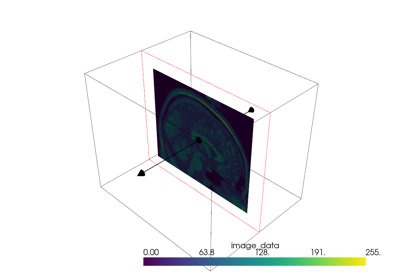

Plotting#

These examples show case many of the possibilities for altering how you display spatial data. Explore these examples to learn how to leverage our powerful 3D plotting routines to perform tasks like:

Adding textures/images draped over a mesh (texture mapping)